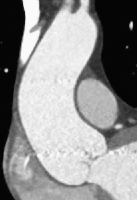

Personalisierte chirurgische Behandlungen bei Erkrankungen der aufsteigenden Aorta // Personalized surgical treatments for diseases of the ascending aorta

Journal für Kardiologie - Austrian Journal of Cardiology 2026; 33 (3-4): 64-69 Volltext (PDF) Summary Abbildungen